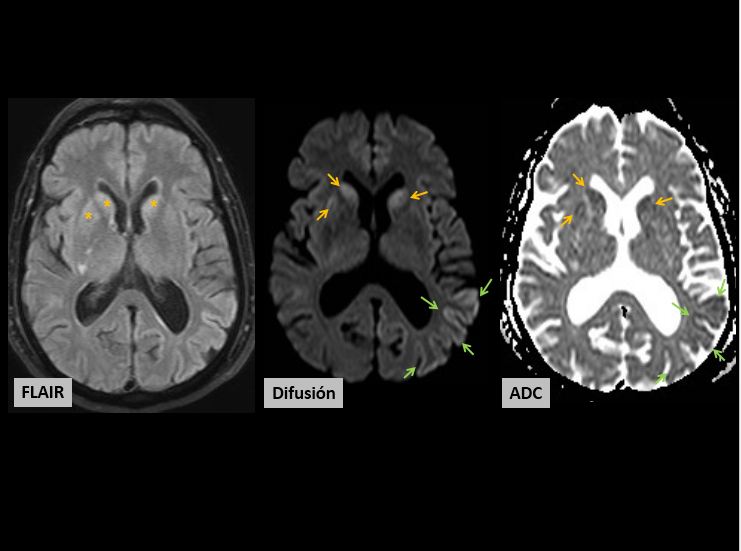

Figura1:

-FLAIR: casi imperceptible. Hiperintensidad de señal en cabeza de caudados y putamen derecho (parte más anterior)

-Difusión: secuencia más sensible. Restringen (+++), además es llamativa la afectación de la cortesa cerebral

-ADC: verdadera restricción (no es efecto T2)